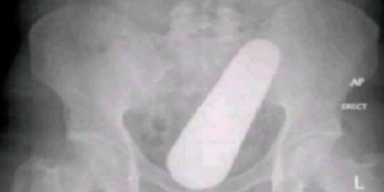

Ratlos begann das medizinische Personal mit Untersuchungen, bis es bei einer Röntgenaufnahme einen großen Fremdkörper in seinem Rektum fand. Der Mann aus Baranoa (Kolumbien) wurde daraufhin betäubt, damit die Ärzte den Fremdkörper entfernen konnten, wobei sich schnell herausstellte, dass es sich um eine Gurke handelte.

Nach der Operation erklärte der Mann den behandelnden Ärzten, dass er keine Ahnung habe, wie die mysteriöse Frucht dort hineingekommen sein könnte, und dass er sogar Angst vor Zäpfchen habe. Er stellte die Theorie auf, dass die Gurke in seinem Verdauungssystem aus einem Samen gewachsen sein könnte, da er zu Hause viel Gurke isst.